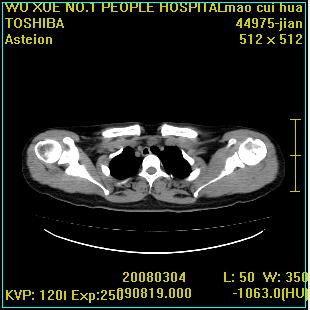

标题: CT12025:男,50岁,左肩活动受限半年。

肩关节骨质破坏呈小囊状,其周软组织轻度肿胀,余未见异常。

考虑:肩袖损伤。建议mri。

左侧肱骨头密度不均匀,高低混杂,周围软组织略肿胀,考虑结核性病变。

左侧肱骨头密度不均匀,高低混杂,髓腔密度稍高,周围软组织略肿胀,肌间隙模糊,考虑慢性骨髓炎可能。密切结合临床!